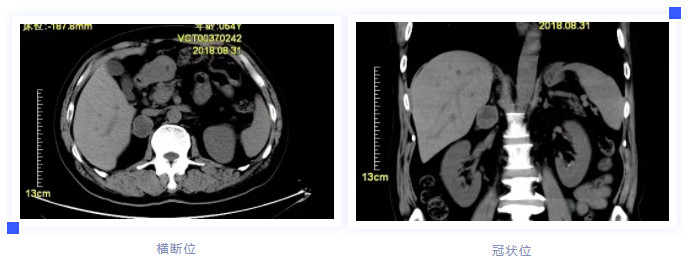

报告可见:嗜铬细胞瘤分泌的儿茶酚胺类激素水平显著增高。进一步CT扫描,见右肾上腺区占位性病变(见下图)。至此明确了疾病的诊断为肾上腺髓质肿瘤(嗜铬细胞瘤)。

经手术治疗,患者症状明显改善,术后病理亦证实为肾上腺嗜铬细胞瘤(见下图)。